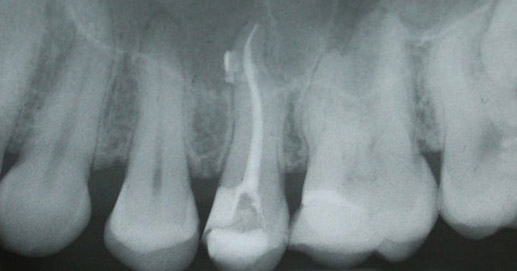

Per verificare la completezza dell’otturazione, che deve arrivare fino all’apice della radice, viene effettuato anche un controllo radiologico.

Il tessuto rimosso dai canali radicolari viene, quindi, sostituito con materiali di riempimento termoplastici (cioè modellabili con il calore) e con cementi che servono da collante tra il dente ed il materiale utilizzato per l’otturazione.

L’utilizzo congiunto del materiale termoplastico e del cemento riempie completamente e tridimensionalmente i canali radicolari sigillando così tutti gli spazi residui ed eliminando la presenza di spazi vuoti che potrebbero, in seguito, essere colonizzati dai batteri.